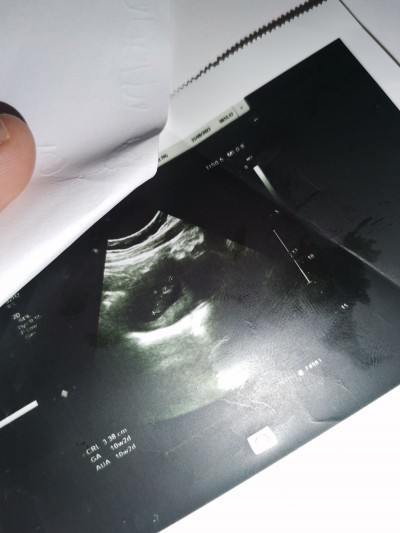

Ben doktora gidiyordum çocuk için 1 ay 14 gün önce doktora gittim bana fitil falan verdi şimdi hamileyim dün doktoruma gittim 10 hafta 2 günlük dedi ultrason kağıdındada öyle yazıyor kafam karıştı eğer doktora gittiğimde varsa niye demedi öyle fitil ilaç kullandım internetten bakıyorum 10 haftalık çocuğun ultrasonuna benimki gibi değil niye böyle oldu bilmiyorum

image

Ultrason cihazındaki değerler doğrudur genelde çünkü son adetini bilmeyenlerde bile kaç haftayla uyumluysa söylüyor hemen fitil ve ilaç kullandınız Allah'tan çocuğa birşey olmamış valla